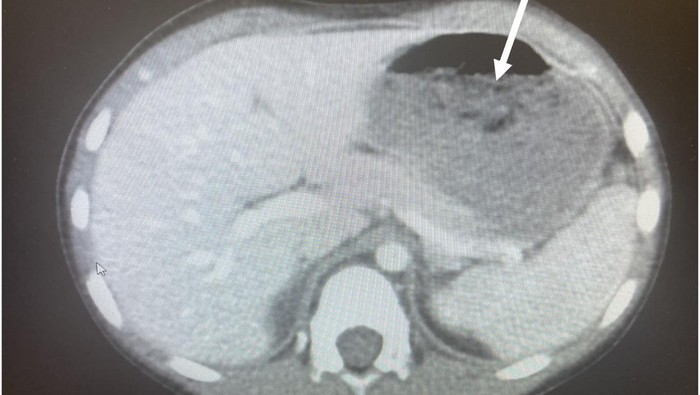

Dokter memeriksa 'bezoar' atau dikenal sebagai benda asing yang tidak dapat dicerna yang cenderung ditelan oleh anak-anak. Tim medis yang dipimpin oleh Dr. Chizite Iheonunekwu dari Cleveland Clinic, menemukan perutnya yang bergetah dengan hasil scan yang memperlihatkan benda yang besar.

Penampakan x-ray dalam tubuh bocah 5 tahun yang menelan 40 buah permen karet. Foto: JEM Reports |